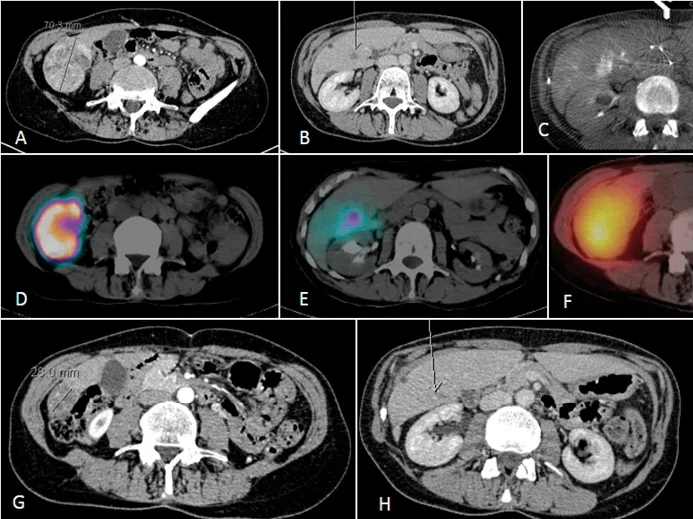

Figure 2. Exemple de traitement chez une patiente avec CHC et thrombose tumorale.

A. Scanner initial montrant un CHC de 7 cm.

B. Thrombose de la branche portale sectorielle postérieure.

C. Cone Beam CT pendant l’artériographie préparatoire montrant une hypervascularisation de la thrombose tumorale.

D et E. Scintigraphie après injection de macro-agrégats d’albumine marqués au technétium montrant une fixation tumorale et de la thrombose. La dose délivrée prévue à la tumeur était de 406Gy.

F. Scintigraphie après injectiondes microsphères marquées à l’Yttrium-90 confirmant la fixation tumorale.G et H. Réponse à 6 mois avec dévascularisation de la lésion,réponse objective, et revascularisation de la branche portale. La patiente a ensuite bénéficié d’une résection hépatique, avec nécrose complète de la lésion et de la thrombose. Elle est en rémission à 6 mois de la chirurgie.